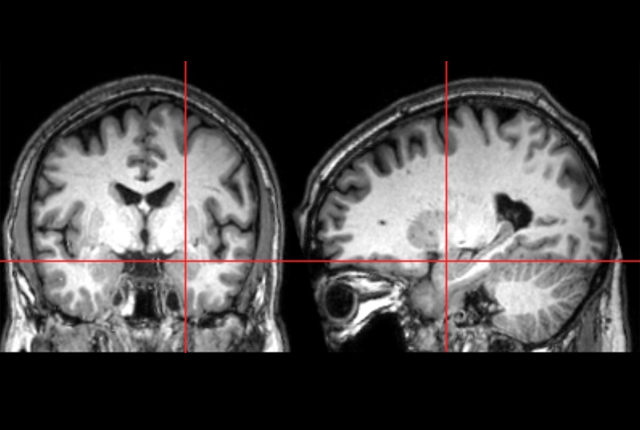

Researchers have long known the amygdala is significantly larger in school-age children diagnosed with autism, but it was unknown precisely when that enlargement occurs. Now, for the first time, researchers from the Infant Brain Imaging Study (IBIS) Network, which includes the University of Washington, used magnetic resonance imaging (MRI) to demonstrate that the amygdala grows too rapidly in infancy. Overgrowth begins between 6 and 12 months of age, before the characteristics of autism fully emerge, potentially enabling the earliest identification of this condition.

The new study, published March 25 in the American Journal of Psychiatry, is the first to document amygdala overgrowth before autism appears clinically. The research was conducted through the IBIS Network, a consortium of 10 universities in the United States and Canada.

“We also found that the rate of amygdala overgrowth in the first year is linked to the child’s social deficits at age two,” said first author Mark Shen, assistant professor of psychiatry and neuroscience at the University of North Carolina Chapel Hill and faculty of the Carolina Institute for Developmental Disabilities. “The faster the amygdala grew in infancy, the more social difficulties the child showed when diagnosed with autism a year later.”

Earlier studies by the IBIS team and others revealed that even though the social deficits that are a hallmark of autism are not present at 6 months of age, infants who go on to develop autism have altered attention to visual stimuli in their surroundings in the first year of life. The authors hypothesize that these early alterations with processing visual and sensory information may place increased stress on the amygdala, leading to its overgrowth.

“We are getting closer to understanding why autism occurs by learning more about brain growth alterations early during development, in this case how amygdala growth may be influenced by early sensory processing difficulties and, conversely, how amygdala growth alterations may influence a baby’s interaction with their environment,” said Dr. Stephen Dager, professor of radiology in the UW School of Medicine and an adjunct professor of bioengineering.